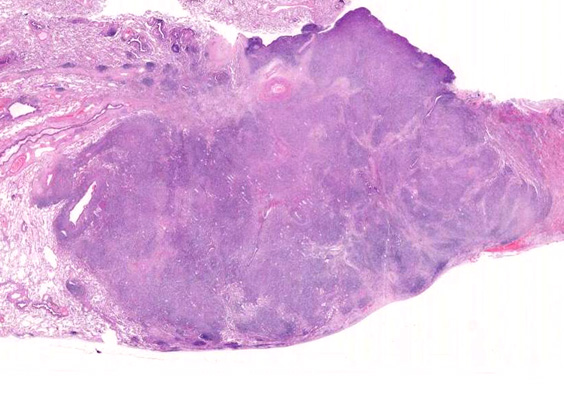

• 組織学的に,LyGは,様々な割合のリンパ球と大きなEBV+芽球からなる血管中心の浸潤を特徴としており,その中にはHRSに類似した特徴を示すものが出現する. 血管浸潤とそれに伴う多量の凝固壊死が典型的な所見である.

• 疾患名に肉芽腫という言葉がはいっているが, 肉芽腫は皮膚以外の病変には見られない。興味深いことに,皮膚病変は,EBV+が明瞭でないB細胞, 毛包炎, 非壊死性肉芽腫によって特徴付けられ, サイトカインを介した事象であると考えられている。

血管周囲性に大型類円形核や不整形核をもつ腫瘍細胞がシート状密に浸潤増殖している. Mitosisが多く認められる.細血管閉塞や破壊の所見がある.

間質にもシート状の腫瘍細胞浸潤がある. 大小 pleomorphicな傾向.(A, B). necrosisが認められる(C). 細気管支上皮直下まで密な浸潤あり, 小型リンパ球が混在している.(D)

血管中心性浸潤. 障害された血管内に血栓が形成されている.CD20陽性細胞がシート状密に浸潤, CD3陽性T細胞が多く混在している. EBER-ISH陽性 EBV感染細胞が多数認められ, >50 hpf, 定義より Grade3となる. 陽性細胞のサイズは大小さまざまであることに注意.